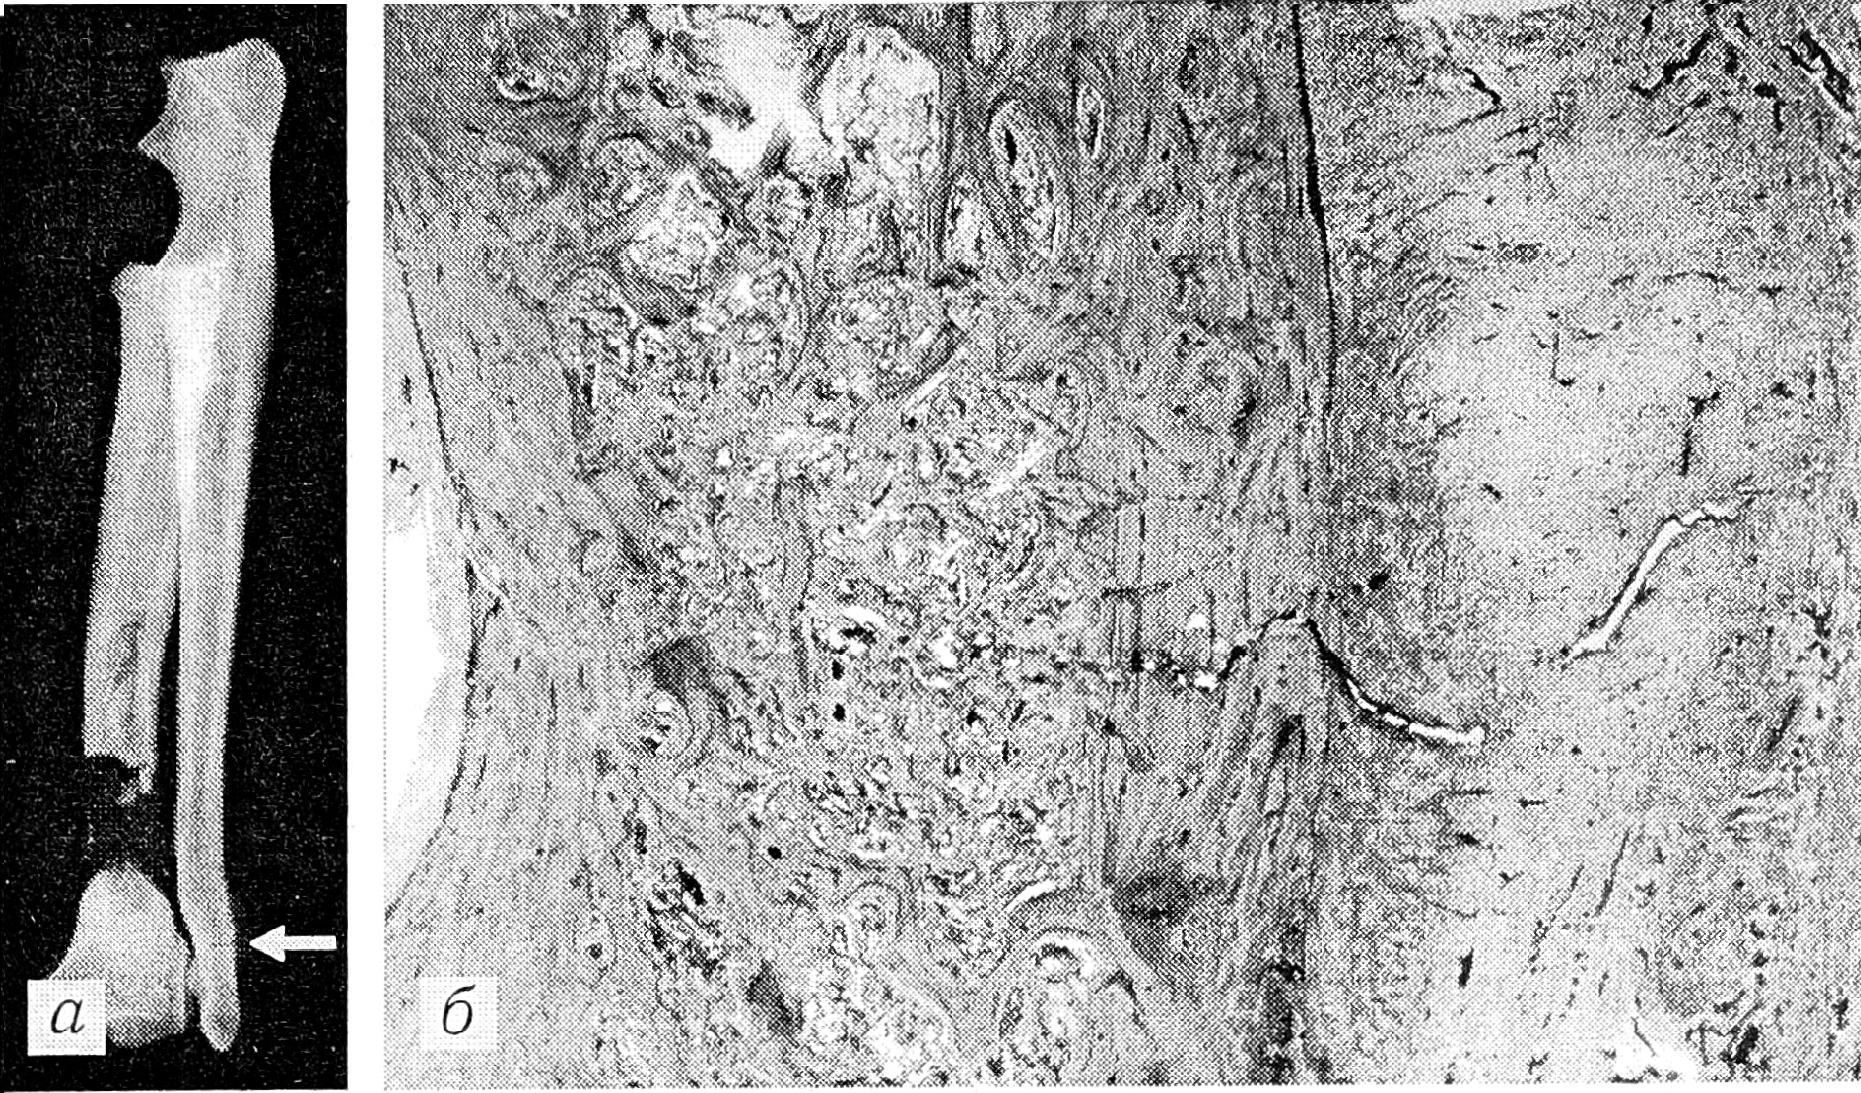

Результаты и обсуждение. Изучение динамики рентгенологических и морфологических показателей (форма и структура костей) в эксперименте показало, что функциональное перенапряжение неповрежденной кости уже ко 2—3-м суткам активизирует периостальное и эндостальное костеобразование, однотипное репаративной реакции при переломах. Этот процесс костеобразования, протекающий на фоне острого расстройства внутрикостного кровоснабжения и называемый репаративной реакцией на перенапряжение (рис. 1), приводит к локальному утолщению кости — гиперостозу.

Рис. 1. Репаративная реакция на перенапряжение (16-е сутки функциональной перегрузки).

Окраска гематоксилином и эозином. Ув. 12.

a — рентгенограмма: стрелкой показано поперечное просветление на уровне метадиафиза локтевой кости; б — гистотопографический препарат (тот же случай): надлом компактной кости с частичным повреждением периостального и эндостального регенерата (окраска гематоксилином и эозином. У в. 20).